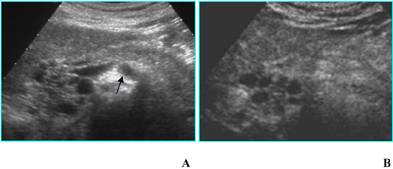

Adenocarcinoma in a 85-year-old woman who presented with diabetes at sudden onset. A. B-mode US (transverse scan) shows a hypoechoic mass, located in the head of the pancreas (asterisks), 3.5 cm in diameter. Splenic vein (arrow) is visible. B. On CEUS the mass is hypoechoic (asterisks) compared to the surrounding parenchyma in the arterial phase. C. MDCT curved reformatted image depicts pancreatic duct dilatation and hypodense lesion in the head of the pancreas.

Fig 2

Adenocarcinoma in a 45-year-old woman who presented with jaundice. A. B-mode US (trasverse scan) shows a hypoechoic mass in the head of the pancreas, 4 cm in diameter. Main pancreatic duct dilatation (arrow) is visible. B. On CEUS the mass is isoechoic in the arterial phase.

a) Ductal adenocarcinoma is usually hypoechoic (absent or poor enhancement compared to normal pancreatic parenchyma), because of its scanty vascularization [2] (Fig. 1). In particular, tumors in which the size of the hypoechoic area is unchanged on CEUS have clear margins with no infiltration or inflammation; tumors in which the size of the hypoechoic area is reduced on CEUS have blurred margins with infiltration of cancerous cells and inflammation. CEUS may be a tool for evaluating pathologic changes of pancreatic cancer and may provide useful information in the pre-treatment phase [2].

Ductal adenocarcinoma is rarely isoechoic (enhancement similar to normal pancreatic parenchyma); this pattern is due to a moderate vascularization (Fig. 2) occurring in some histotypes (anaplastic carcinoma and acinar cell carcinoma) [3]. The isoechoic pattern is often observed in focal pancreatitis too [4]: therefore, CEUS is not always able to accurately differentiate adenocarcinoma from focal pancreatitis, as well as CT and MR [5].